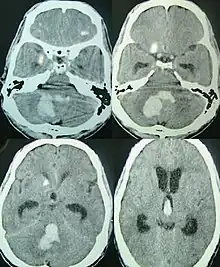

CT scan of a spontaneous intracerebral bleed, leaking into the lateral ventricles

Spontaneous ICH with hydrocephalus on CT scan[10]

Intraparenchymal hemorrhage can be recognized on CT scans because blood appears brighter than other tissue and is separated from the inner table of the skull by brain tissue. The tissue surrounding a bleed is often less dense than the rest of the brain because of edema, and therefore shows up darker on the CT scan.[20] The oedema surrounding the haemorrhage would rapidly increase in size in the first 48 hours, and reached its maximum extent at day 14. The bigger the size of the haematoma, the larger its surrounding oedema.[21] Brain oedema formation is due to the breakdown of red blood cells, where haemoglobin and other contents of red blood cells are released. The release of these red blood cells contents causes toxic effect on the brain and causes brain oedema. Besides, the breaking down of blood-brain barrier also contributes to the odema formation.[22]